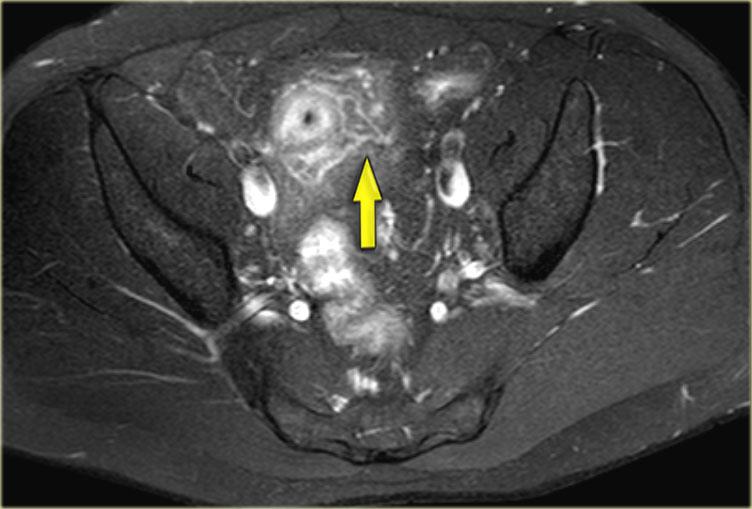

Bệnh Crohn

Bên trái là hình ảnh một bệnh nhân có rò quanh hậu môn trong bối cảnh bệnh Crohn.

Tiếp tục xem hình ảnh coronal.

Trên hình ảnh coronal, hình ảnh dày thành ruột được ghi nhận rõ ràng.

Hình ảnh cắt ngang xóa mỡ cho thấy tình trạng viêm xuyên thành với sự thâm nhiễm vào lớp mỡ mạc treo.